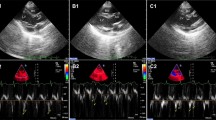

Echocardiography

All patients had a clinically indicated pre-operative transthoracic echocardiogram, using a Vivid S6, 7, or E9 ultrasound system (GE Vingmed Ultrasound, Horten, Norway). Images were obtained by professional echosonographers, and reviewed offline by a European Association of Cardiovascular Imaging accredited cardiologist. Left ventricular (LV) and left atrial (LA) chamber volumes were derived from a biplane method of discs using the apical 4-chamber and 2-chamber views[13]. Cardiac output measurements were calculated applying the heart rate recorded during the apical 4-chamber view. Ejection fraction (EF) was graded according to the European Association of Echocardiography/American Society of Echocardiography recommendations as preserved (> 50%)[14]. LV mass was calculated according Devereux et al.[15], whereas LV volume/mass ratio was calculated at end-systole (LVESV/LV mass)[16].

Diabetes was evident from the high fasting levels of glycated hemoglobin (HbA1c) (58 ± 4 mmol/mol in DM group, normal below 48 mmol/mol) and fasting plasma blood glucose levels (10.0 ± 1.0 mmol/L in DM group, normal below 6.1 mmol/L) (Table 1). All patients had preserved EF (> 50%), and no differences in blood pressures, heart rate, cardiac dimensions, LV mass or LV volume/mass ratio were observed between both groups, suggesting normal systolic function and no additional structural remodeling in DM patients with CAD compared to the non-DM patients with CAD. Although almost all patients were previously diagnosed with hypertension, the incidence was not different between non-DM and DM patients, whereas non-hypertensive blood pressure values indicate the effectiveness of the blood pressure lowering treatment. In contrast, diastolic function was reduced in DM compared to non-DM patients (Table 1) as indicated by a significantly slower early filling time (prolonged early deceleration time, p < 0.05), by a significantly elevated marker of ventricular filling pressures (increased E/e’, p < 0.05) and by the tendency to slower early and late filling velocity (increased E and A, p = 0.05 and p = 0.08, respectively).

Impaired relaxation in human right atrial diabetic myocardium at rest

Our in vivo echocardiography data and our ex vivo cardiac muscle data confirmed both preserved contractile function with no development of structural cardiac hypertrophy in diabetic patients with preserved EF. Echocardiography of the left ventricle also revealed a slower early filling time (prolonged deceleration time) and higher filling pressures during early filling (increased E/e’) with a tendency to slower early and late filling velocities (E and A, respectively), which in the isolated right atrial muscles were accompanied by prolongations of early and late relaxation (decreased -dF/dtmin and prolonged Tau). Together these data indicate reduced diastolic function due to impaired relaxation and increased myocardial stiffness of the heart in the diabetic population with preserved EF. This is consistent with previous echocardiography findings in type 1 and type 2 diabetic patients[2, 23] and with functional myocardial studies in type 1[24] and type 2 diabetic animal models[25], however the myocardial diastolic dysfunction observed in animal models was always accompanied by systolic dysfunction. On the contrary, Reuter et al. have reported no difference in the rate of relaxation or the contractile function of right atrial cardiac muscles from type 2 diabetic patients undergoing CABG[26]. However, the contractile and relaxation measurements reported in that study were much lower in magnitude when compared to values reported in other studies using human right atrial cardiac muscles[27, 28] and our study (Table 2). This may be related to tissue degradation in their samples due to prolonged loading with a fluorescence indicator, while our experimental measurements were obtained within 90 minutes after dissection.